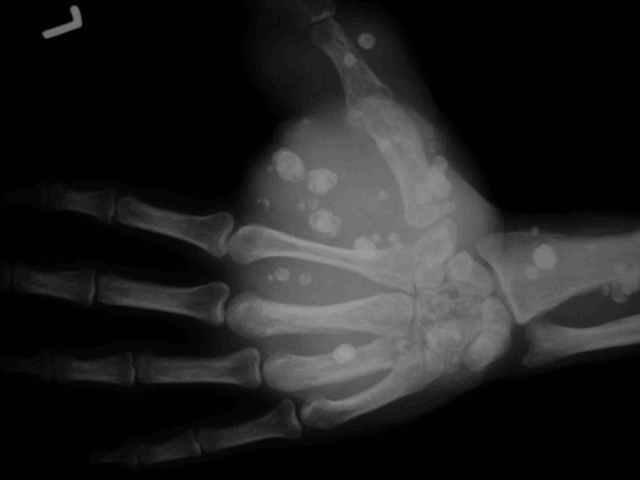

Гемангиома кисти

Нужен совет. Мужчина средних лет, деформация кисти с детских лет, а в поликлинику обратился за инвалидностью. Кисть вполне функциональна и безболезненна, боли появляются только при сильном напряжении кисти.Жду ответа, с наилучшими пожеланиями,Евгений Чекашкин